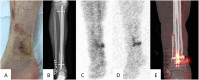

Fracture-related infection (FRI) is a severe complication after bone injury and can pose a serious diagnostic challenge. Overall, there is a limited amount of scientific evidence regarding diagnostic criteria for FRI. For this reason, the AO Foundation and the European Bone and Joint Infection Society proposed a consensus definition for FRI to standardize the diagnostic criteria and improve the quality of patient care and applicability of future studies regarding this condition. The aim of this article was to summarize the available evidence and provide recommendations for the diagnosis of FRI. For this purpose, the FRI consensus definition will be discussed together with a proposal for an update based on the available evidence relating to the diagnostic value of clinical parameters, serum inflammatory markers, imaging modalities, tissue and sonication fluid sampling, molecular biology techniques, and histopathological examination. Second, recommendations on microbiology specimen sampling and laboratory operating procedures relevant to FRI will be provided. LEVEL OF EVIDENCE:: Diagnostic Level V. See Instructions for Authors for a complete description of levels of evidence.